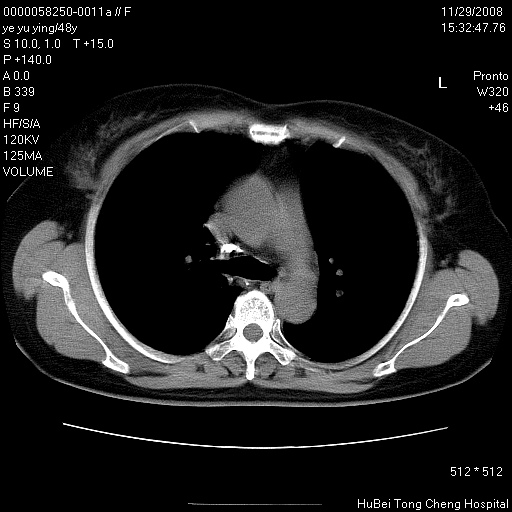

以下是引用zsl6918在2008-11-29 21:47:00的发言:[br]恶性肿瘤病史,转移瘤首先考虑。脂肪肝,胆囊结石。

以下是引用huenhao在2008-11-29 22:11:00的发言:[br]脂肪肝,胆囊结石。左肺病灶建议定期复查。

以下是引用liuyue在2008-11-30 5:44:00的发言:[br]1.左肺病变,首先考虑感染性病变,转移待排;建议治疗后复查。[br]2.肝脏密度普遍减低,考虑与化疗有关。[br]3.胆囊结石.